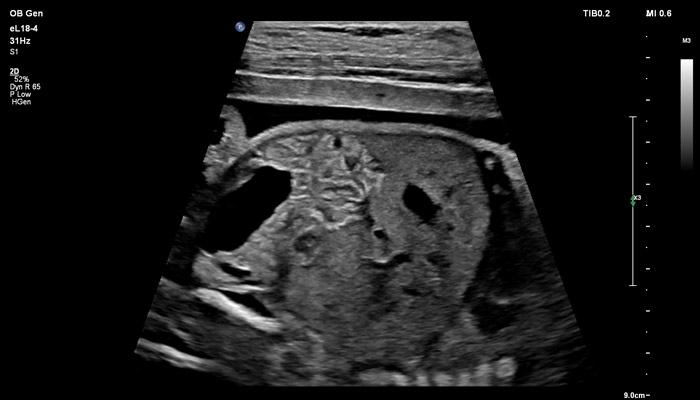

Начало новой жизни - это всегда особое время! Ультразвуковые решения Philips в области акушерства разработаны для того, чтобы позволить врачам сосредоточиться на здоровье каждой будущей мамы. Разработанные для обеспечения клиницистов дополнительной информацией ультразвуковые решения Philips позволяют получать не только детальную визуализацию анатомии плода уже в первом триместре, но и помогают оптимизировать рабочий процесс врача. Применение eL18-4 в I триместре беременности Сегодня ультразвуковая диагностика используется для выявления генетических аномалий, внутриутробных пороков, оценки жизнеспособности плода и определения срока беременности, как наиболее эффективный метод. Ультразвуковое исследование плода в первом триместре (до 13 недель 6 дней беременности включительно) является наиболее точным методом. В течение многих десятилетий трансвагинальный метод ультразвукового исследования был «золотым стандартом» диагностики в акушерстве. Сегодня линейный матричный датчик может стать альтернативой общепринятому трансвагинальному методу оценки состояния плода и репродуктивных органов женщины. Детальная анатомия плода и ранняя диагностика пороков в I триместре Ультразвуковое исследование является основным методом визуализации для оценки врожденных аномалий плода. Линейный матричный датчик eL18-4 позволяет получить детальную информацию об анатомии плода и выявить пороки на ранней стадии развития. Сверхширокополосная PureWave матрица датчика генерирует частоты в диапазоне 2-22 МГц, что формирует одинаково высокоинформативные, четкие изображения по всей глубине сканирования до 14 см.

До введения высокочастотных линейных датчиков точная ультразвуковая диагностика мочевой системы плода была доступна в основном после 16-17 недель беременности. Новая технология еL18-4 позволяет проводить раннюю морфологическую оценку плода уже в первом триместре. Клинический случай с применением eL18-4 демонстрирует, что кортико-медуллярная дифференцировка почек плода возможна на 14 неделе беременности”.

Использование линейного матричного датчика eL18-4 при осмотре беременных в I триместре, особенно на ранних сроках, позволяет ограничиться трансабдоминальным сканированием вместо трансвагинального и при этом получить максимально полную диагностическую информацию. Отсутствие полостного исследования чрезвычайно важно для соблюдения принципа ALARA – использования минимальной необходимой мощности для безопасности пациента. Благодаря применению мультичастотного датчика с диапазоном от 2 до 22 МГц через переднюю брюшную стенку хорошо определяется эмбрион длиной 3 мм, что соответствует шестой неделе беременности. В конце I триместра с eL18-4 достаточно отчётливо визуализируется четырёхкамерный срез сердца, мочевой пузырь и сосуды пуповины, которые, как правило, определяются только при трансвагинальном сканировании.

Во II триместре беременности высокая разрешающая способность eL18-4 позволяет детально изучить структуру органов и тканей и увидеть многие нюансы, которые при работе другими датчиками не обнаруживались или становились очевидны в более поздние сроки. Например, у 19-недельного плода визуализируется перегородка носа, мышцы языка, диафрагма между грудной и брюшной полостью, на 20-й неделе чётко определяются оболочки спинного мозга и уретра, а на 24-й – хорошо дифференцируются корень лёгкого, борозды и извилины мозжечка и многие другие структуры.